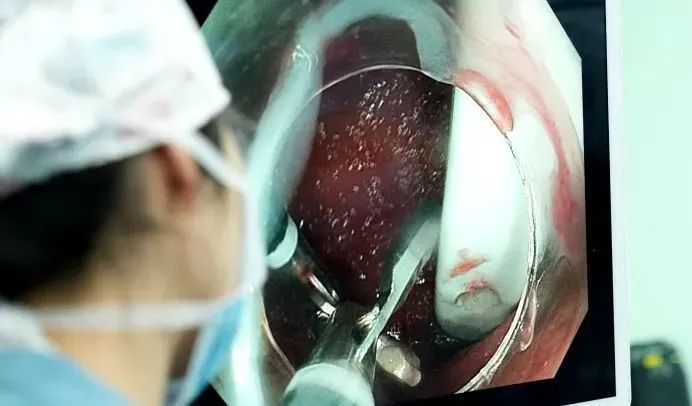

由于勺子表面太过光滑,又长又硬,卡的角度极为刁钻,好不容易圈套器圈住了柄部,一用力,就从光滑的勺面脱了出来……套不住,根本套不住!圈套器反复滑脱,异物钳难以抓牢光滑勺面。

时间分秒流逝,周平红教授果断启用创新方案——双钳协同术。

首先,经内镜通道送入异物钳A,夹持另一把异物钳B抵达勺柄处;

随后,钳B夹住勺柄小孔向下推送,使勺体与镜身平行;双钳配合把整个勺子从狭窄危险的十二指肠区域,慢慢拖回到相对宽敞的胃里。

最后,周教授换回更牢固的“套圈”工具,稳稳套住勺柄,最终顺着食道,成功将这把近15厘米长的陶瓷勺子完整地取了出来!